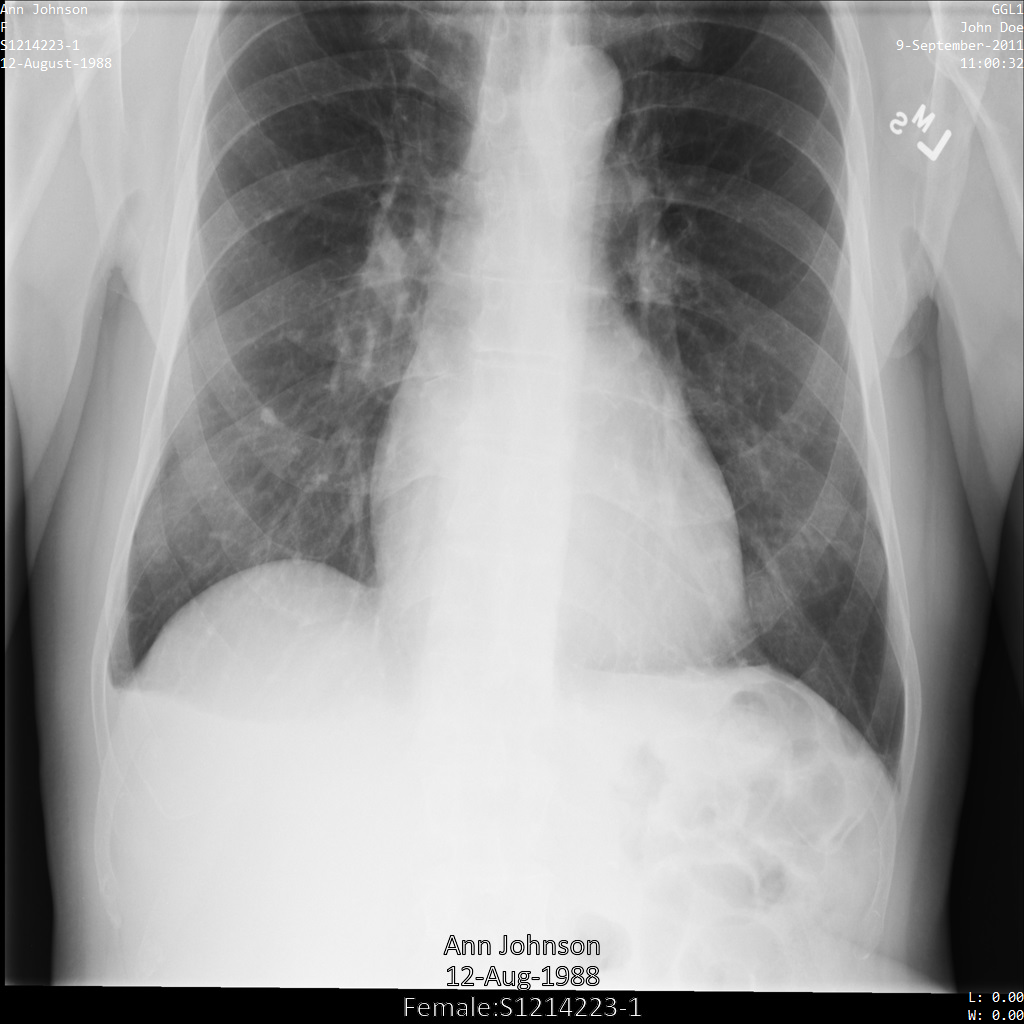

Imagem de amostra

Algumas amostras nesta página contêm uma saída da imagem desidentificada. Cada amostra usa a seguinte imagem original como entrada: É possível comparar a imagem de saída de cada operação de desidentificação com esta imagem original para ver os efeitos da operação:

Depois de desidentificar a imagem usando REDACT_ALL_TEXT

, ela fica assim. Todo o texto gravado na parte de baixo da imagem foi editado.

REDACT_ALL_TEXT